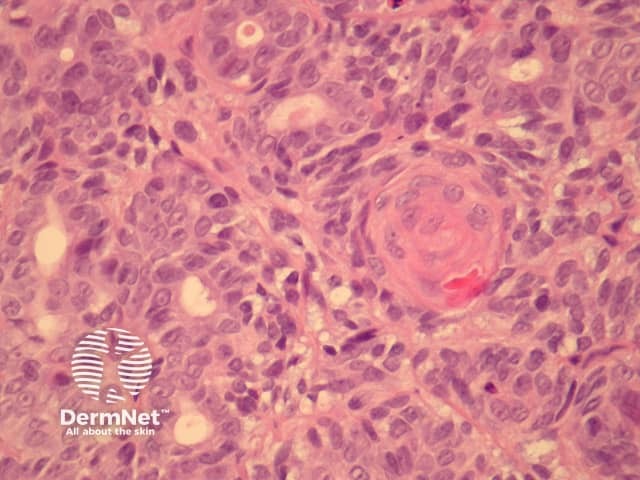

In aggressive digital papillary adenocarcinoma, sections show a dermally based tumour, which may connect with the overlying epidermis (figure 1). The tumour may be cystic, papillary, ductal or solid. The example illustrated here has a predominantly solid and ductal morphology with only focal areas of papillary formation. The cells are basaloid, show enlarged atypical nuclei, large nucleoli and increased mitoses (figures 1-6). Squamous metaplasia within the tumour may be seen (figure 5).

Figure 2